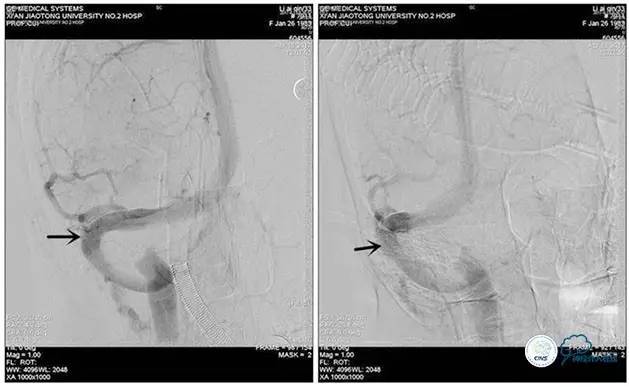

术中造影

5ml/s,总量8ml,压力100~150

手术方案

1、6mm×20mmAviator球囊(Cordis)分段对狭窄部位进行扩张。

2、植入7mm×40mmPrecise自膨支架。

术后造影

术毕远近端压力差为:0